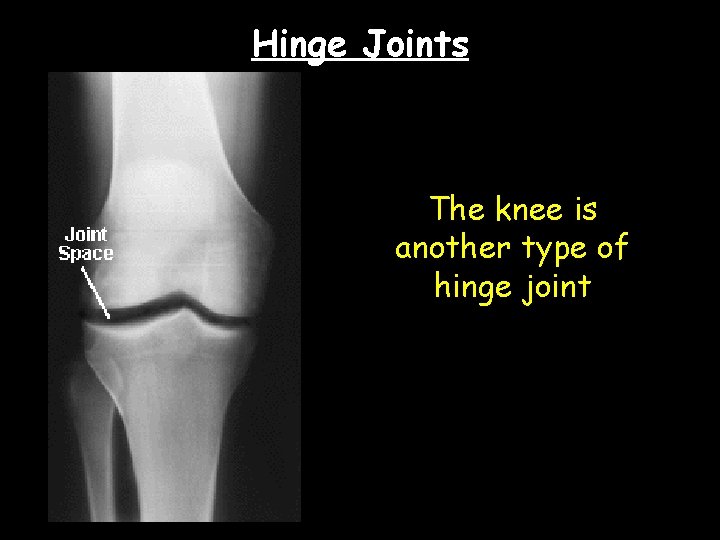

Hinge Joints The knee is another type of hinge joint